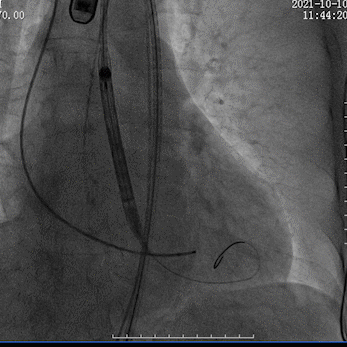

瓣膜回收调整位置

瓣膜再定位

瓣膜植入较深

瓣膜再回收调整